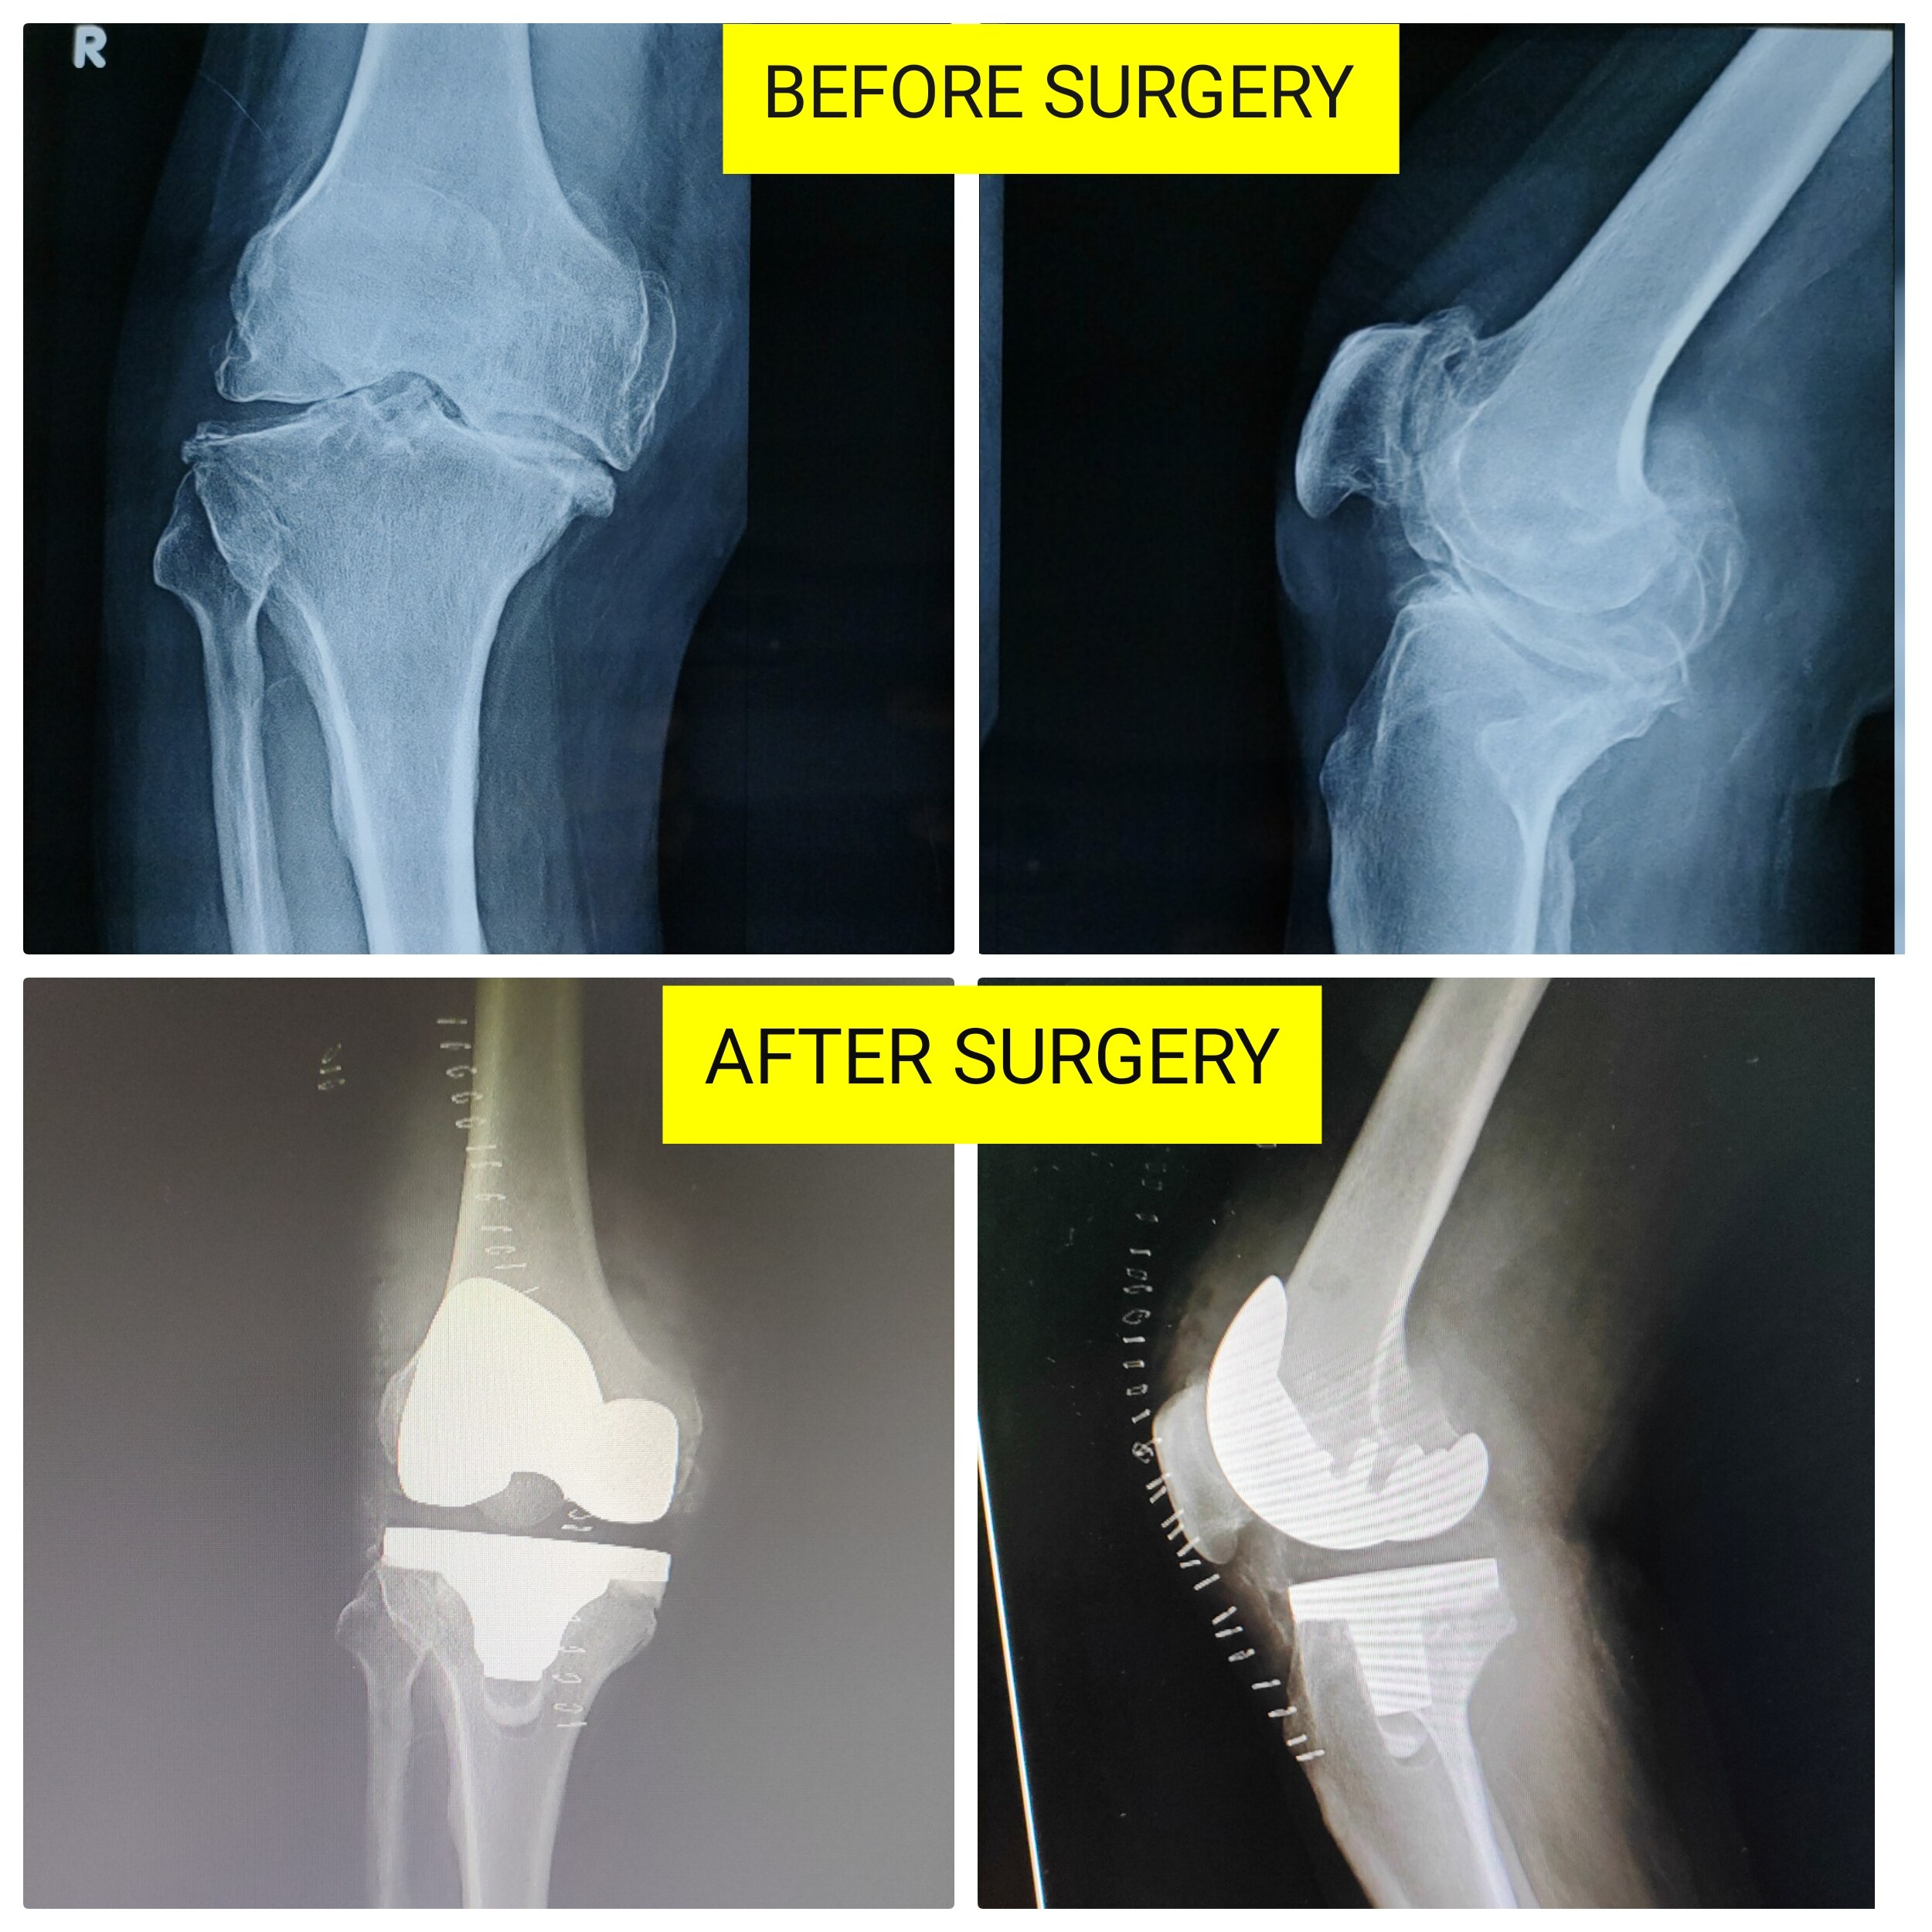

Welcome to the world of orthopedic excellence, where your health and well-being are our utmost priorities. Dr. Chetan Singh , an accomplished orthopedic surgeon, has been a dedicated practitioner in the vibrant city of Bhopal for the past 8 years. His unwavering commitment to providing exceptional orthopedic care has earned him a reputation as a trusted healthcare professional in the region. Meet Dr. Chetan Singh is a highly skilled orthopedic surgeon who has dedicated his career to improving the lives of patients suffering from orthopedic conditions. His educational journey began with the completion of an MBBS degree from Devi Ahilya Vishwa Vidyalaya, Indore, M.P. in 2015, where he laid the strong foundation for his medical expertise. Driven by his passion for orthopedics and a desire to offer the best care possible, Dr.Chetan Singh continued his educational journey. In 2019, he successfully achieved a Master of Surgery (MS) in Orthopedics from Madhya Pradesh Medical Science University, Jabalpur. This rigorous training equipped him with the knowledge, skills, and advanced techniques necessary to diagnose, treat, and manage a wide spectrum of orthopedic conditions.